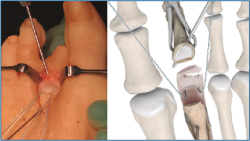

2. Luxamos el dedo a plantar y despegamos cuidadosamente la placa plantar del cuello metatarsal con un periostotomo o un disector de McGlamry (Figura 2).

Es importante exponer el tercio proximal de F1 y cruentar en su aspecto plantar la huella de reinserción de la placa plantar, separando bien las partes blandas a este nivel, para facilitarnos posteriormente la recuperación de las suturas (Figura 4).

Colocamos otra agK en la unión metafisodiafisaria de F1 y realizamos una distracción del espacio MTF en el eje diafisario con ayuda de un distractor (Figura 5).

4. Ahora podemos explorar bien la placa plantar, valorar el tipo de rotura y plantear su reparación.

Lo habitual será reinsertarla en la base de F1. En caso de presentar una atenuación severa o una desinserción parcial mayor del 50%, consideramos más útil desinsertarla completamente y proceder a su reinserción. En caso de encontrar una rotura longitudinal medial o lateral, puede plantearse una sutura longitudinal o la reinserción parcial (Figura 6).

Figura 4. Cruentación de la huella de inserción de la placa plantar en la base de F1.

Figura 5. Distracción metatarsofalángica obteniendo un espacio de trabajo y observando perfectamente la rotura completa de la placa plantar.

Figura 6. Diferentes posibilidades de sutura en función del tipo de rotura.